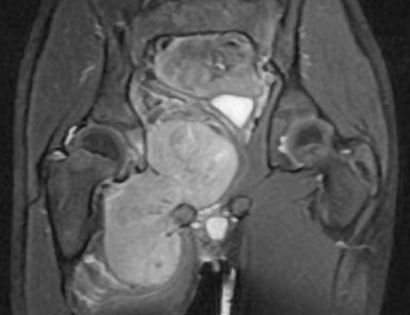

Adductor Compartment MRI

This is an MRI of the thigh region. The tumor is located in the inner right thigh (left-hand side) which is brighter than the surrounding tissues.